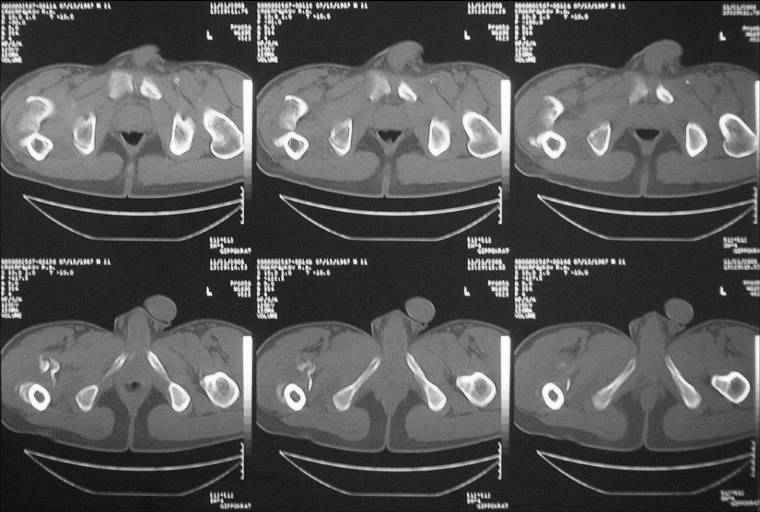

Уважаемые коллеги! Нужен совет.Больной Х., 21 год, ДЗ: ложный сустав вертельной области правого бедра.

Травма 8 мес. назад, ДТП, получил закрытый межвертельный перелом правого бедра. Лечился в городской больнице одного из городов-спутников г. Караганды скелетным вытяжением в течение 3 недель, затем кокситной гипсовой повязкой 2 мес. В настоящее время имеется укорочение конечности на 7 см, умеренная боль в вертельной области; ходит без костылей, полностью нагружая больную конечность, при нагрузке отмечается смещение дистального отломка проксимально примерно на 1,0 см.; объем движений в коленном суставе сохранен; при пальпации отломков боли нет, умеренная патологическая подвижность. Планируем внеочаговый остеосинтез спице-стержневым аппаратом, дистракция до восстановления длины бедра, вторым этапом остеосинтез стержнем Гамма. Есть надежда, что на дистракции пойдет сращение и у больного хватит терпения завершить лечение в аппарате.

Если судить по снимкам, то укорочение кажеться не критическим, но обьективно и на 3D - укорочение на 6-7 см.